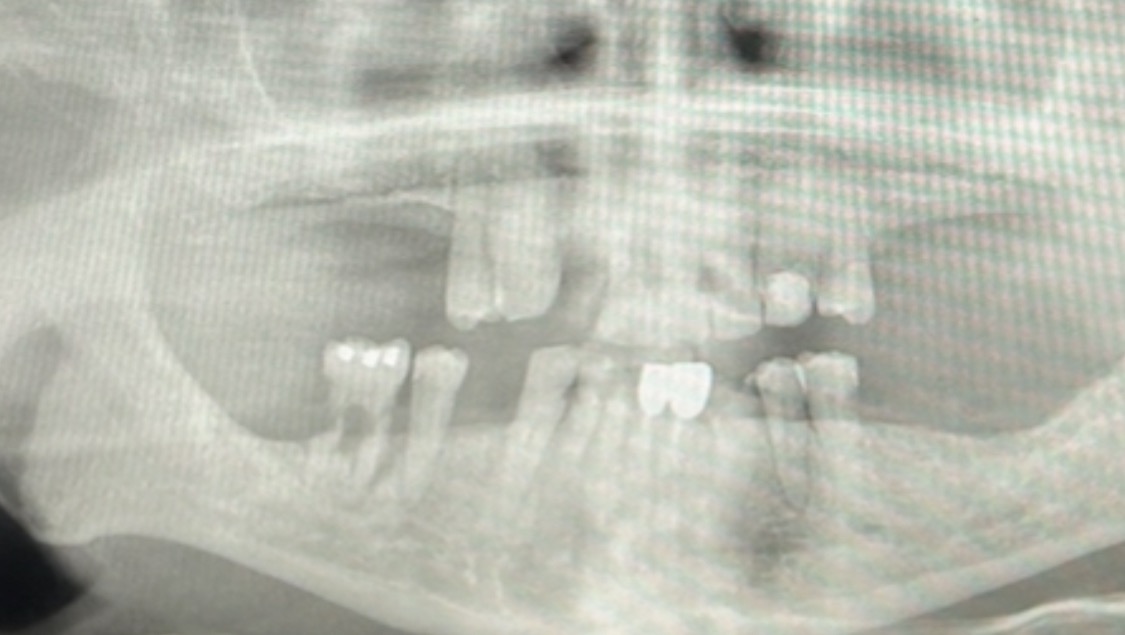

Two years ago in November, I was diagnosed with stage 3 squamous cell in my right lung, started chemo and radiation the next month. Having fatigue and constant coughing makes it very difficult for me to work. After the chemo treatment, I started immunotherapy which was supposed to only have once a month for a year, but shortly after my treatment, I had pneumonia that made me had to stop the immunotherapy treatment. Since then I had 4 pneumonia as a result of having immunotherapy, it causes the inflammation of the lung tissue and I had to stay in bed and cough for most of the year. I am on disability and barely keep our monthly bills paid because of me not able to work. I tried to do food delivery which the time is more flexible given my situation but still having hard time to keep up with my bills. It doesn’t stop here, due to my chemotherapy and radiation that burnt my mouth and throat, I don’t produce much saliva and it makes my eating even more difficult, my teeth are damaged also because of the radiation. With only 14 of my teeth that functions, only little amount of saliva, make it very difficult for me to eat what doctors suggest me to consume, more protein and less carbs, and that makes my recovery even more challenging. Dentist wants me to get partial dentures for my upper and lower missing teeth but it cost about 9,000 dollars which will add on top of my medical bills that I cannot afford.

Last year, due to some paperwork error, Texas Health and Human Services denied my Medicare for three months and I had to fight to get my Medicare back, without the Medicare I was unable to get my treatments. This year, my insurance made my recovery more difficult by having me to pay much more out of pocket, deduction from my disability check, and with only two thousand dollars of dental a year that I already spend four hundred dollars for consultation and x-rays. I can’t afford my dentures, have unpaid around 7,000 dollars cancer treatment bills and upcoming treatment costs. I already maxed out my credit cards because of all these and my credit score is terrible, and I was not able to work during pneumonia and fatigue after the treatments. I have depression, stress and anxiety from all of these but I don’t even have money nor time to treat them.